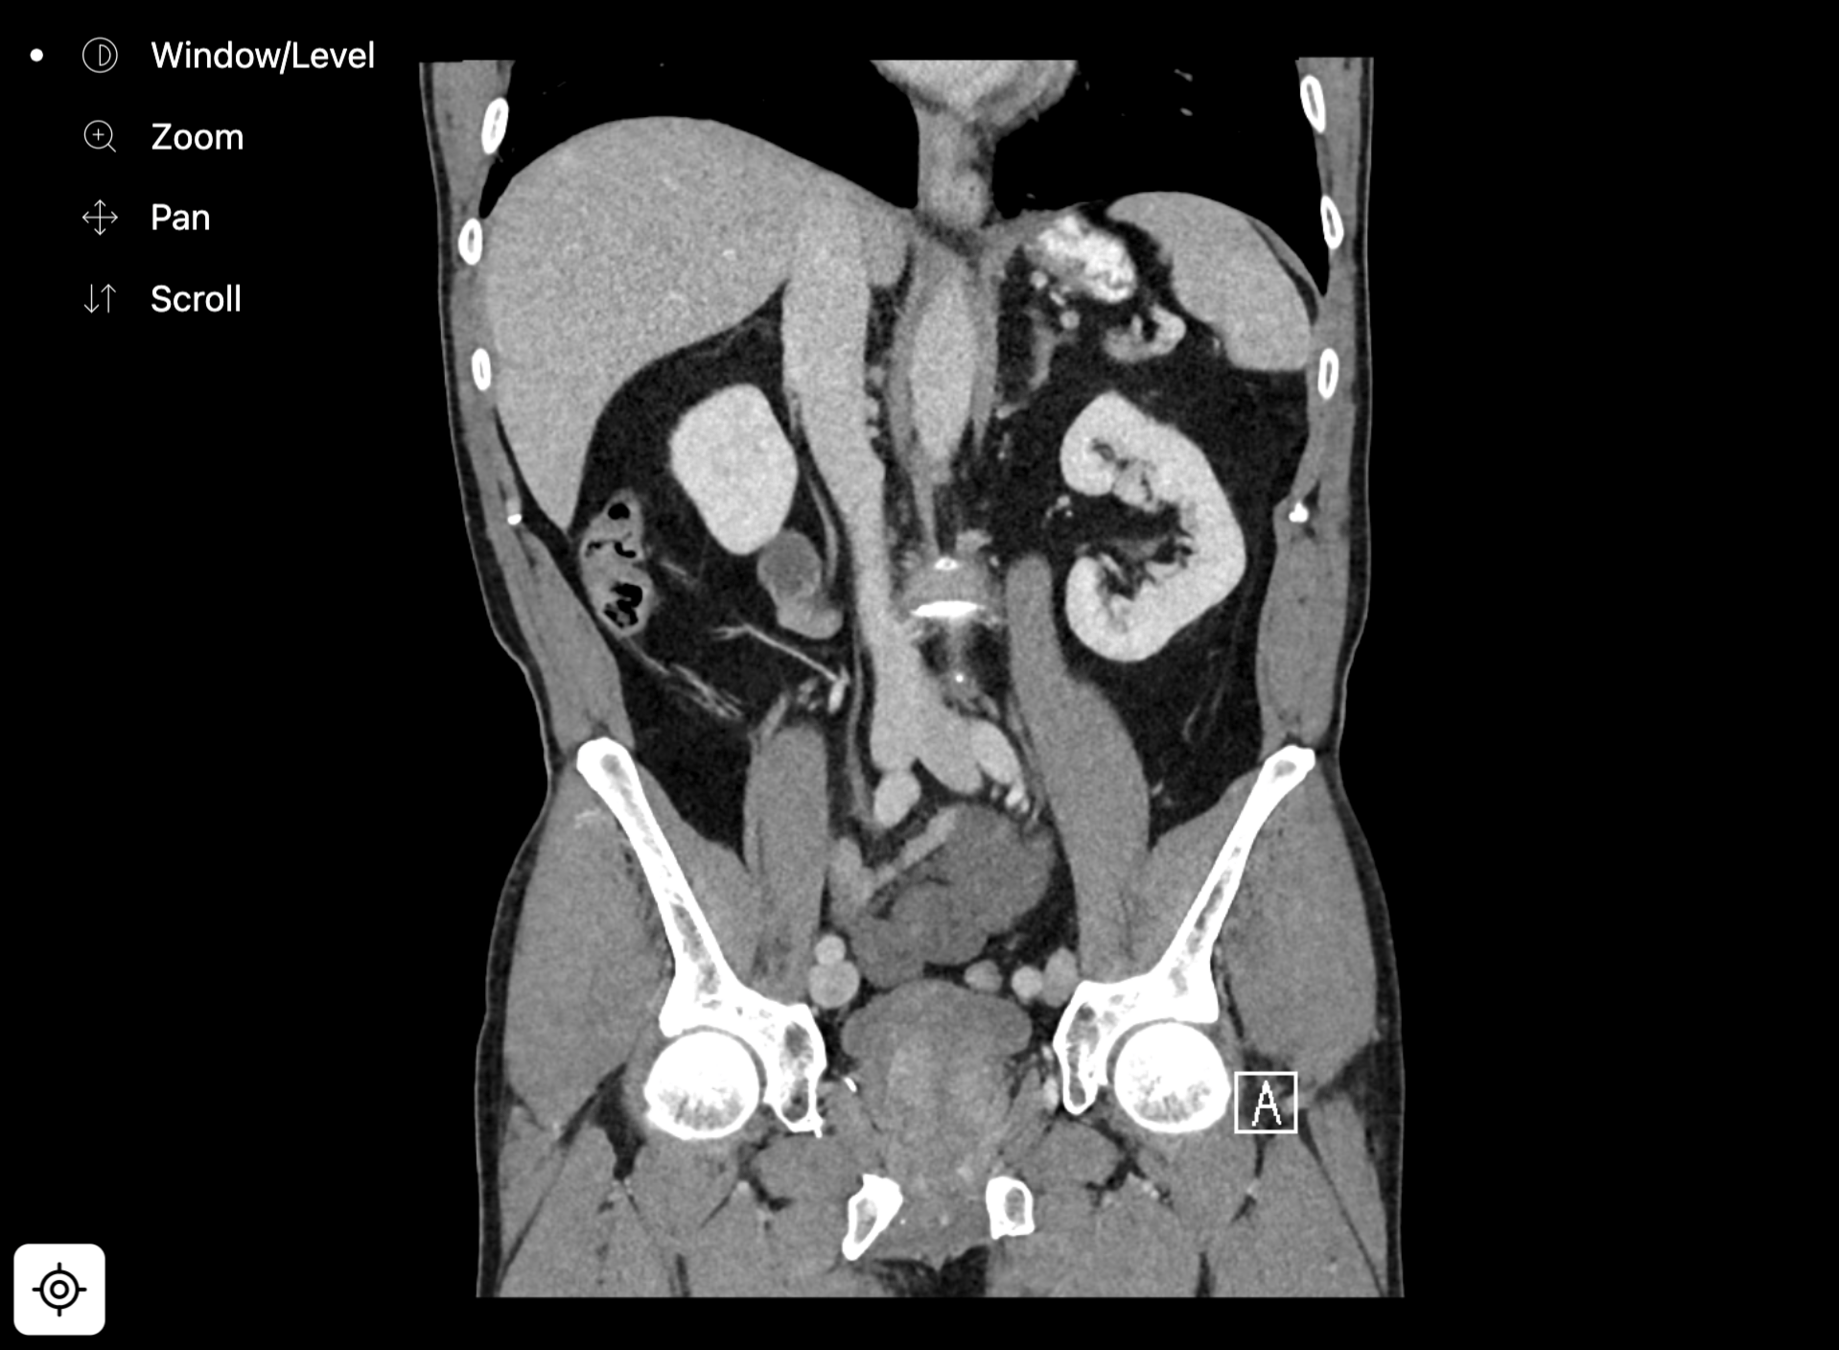

closed loop small bowel obstruction

notice how a single image can't show the entering and exiting transition points?